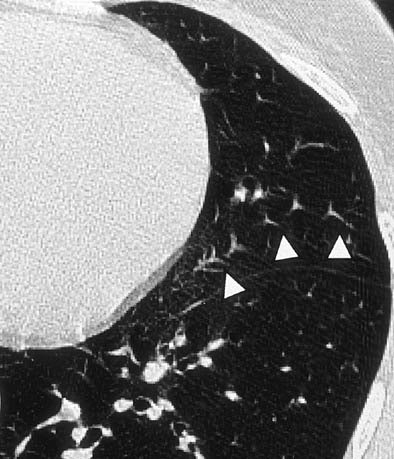

| Twinkling star artifact. Non-ECG-gated CT scan in a 35-year-old woman with recurrent pneumothoraces reveals "twinkling star" artifact (arrowheads). A motion artifact caused by distortion of pulmonary vessels due to cardiac motion is seen in the lingula of the left upper lobe (Radiology, 1999;212:649-654). |

In a 1999 study, Schoepf and colleagues from the University of Munich in Germany aimed to identify the benefits of prospective ECG triggering for examining the lung parenchyma using high-resolution CT (Radiology, September 1999, Vol. 212:3, pp. 649-654).

"You can see that ECG triggering takes care of those twinkling star artifacts adjacent to the left cardiac border," he said of an image projected on the screen. "You get rid of what has been dubbed the tram-track sign, the double appearance of the (lung) fissures, and the double cardiac border."